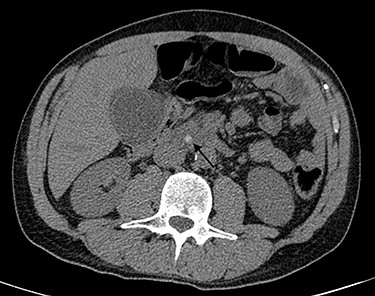

Blood tests performed at admission demonstrated cholestasis and high transaminases. An abdomen computed tomography scan with intravenous contrast was performed, displaying a lithiasic cholecystitis and cholangitis, with a radio-opaque stone in the terminal tract of the CBD (Figs 1 and 2).